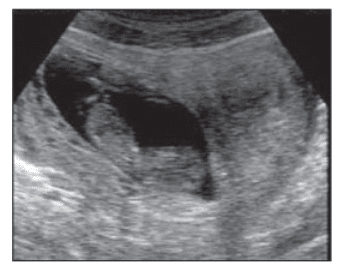

Observa-se ultrassonografia abdominal evidenciando útero bicorno com gestação de 10 semanas. Nota-se cavidade sem feto apresentando decidualização: